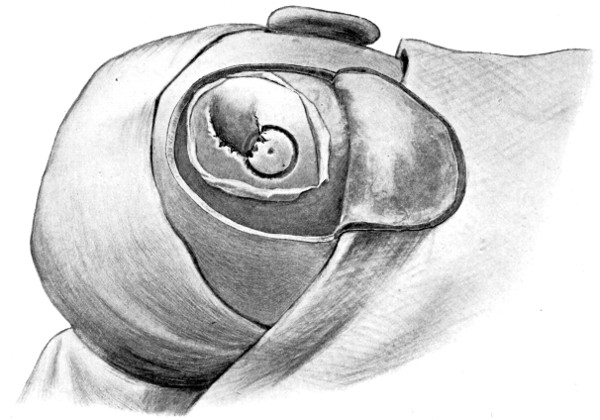

Fig. 20. An Occipital Cephalocele. (For further description, see text.)

1. Occipital cephaloceles—the commonest variety—occupy, anatomically, two positions (1) between the two lower segments of the occipital bone (inferior occipital cephaloceles), often involving the foramen magnum and sometimes complicated by a condition of cervical spina bifida, and (2) between the two upper segments of the occipital bone (superior occipital cephaloceles), occasionally involving the posterior fontanelle.

The tumour may possess a broad base or may be definitely pedunculated. In the former instance the gap in the bone may be of considerable size and the margins everted: in the latter case, the hole may be quite small.

The deformity is frequently associated with other congenital defects—hydrocephalus, microcephalus, spina bifida, hare lip, hernia, and talipes.

Sincipital cephaloceles are usually quite small, but the occipital variety and those situated in[35] the region of the anterior fontanelle frequently attain a great size (see Figs. 20-22).

Fig. 22. An Occipital Cephalocele. (For further description, see text.)

It is not always possible to determine whether the tumour consists of a mere outward protrusion of membranes (meningocele), or whether brain-matter enters into the formation of the tumour (meningo-encephalocele). Fluctuation, translucency, and pulsation are all points to be investigated. All these features are, however, deceptive, and several cases are on record in which operative measures were carried out under the impression that the surgeon had to deal with a pure meningocele, and in which it was afterwards found that brain-matter formed the basis of the swelling.

When the tumour is large, the skin adherent, when no pedicle is present, when fluctuation and pulsation are absent, and when the tumour is of firm consistency, then it is practically certain that brain-matter shares largely in the formation of the tumour. On the[36] other hand, it is not unusual to find that the brain projects markedly outwards without resulting in any symptoms of brain irritation: fluctuation and pulsation are also not infallible signs, since the brain may occupy the base of the tumour, ‘corking-up’ the gap in the bone, or the brain may be so thinned by ventricular distension that a mere shell of cerebral matter lies beneath the scalp-covering.

Looking at the question from all points of view, it may be accepted that most cephaloceles contain either true brain-matter or the mixed epiblastic and mesoblastic elements described by Lyssenkow.

The following case serves to illustrate some of these facts:[9]—

The child was 3 months old, and presented a tumour, the size of an orange, situated between the occipital protuberance and the nape of the neck. The mass was pedunculated, the stalk being about the size of a four-shilling piece in diameter. It was soft, translucent, irreducible, and swelled up on coughing. An attempt at removal was carried out, and, after incising the outermost layers, three ounces of cerebro-spinal fluid escaped. A second tumour was then found occupying the base of the swelling. This was also punctured, more fluid escaping. Both sacs were cut away and the wound sewn up. Death occurred on the third day, preceded by convulsions, retraction of the head and neck, and high fever. The autopsy showed that the fontanelles were widely open, the anterior measuring 4 inches from side to side and 21⁄2 from before backwards. The bones of the vault were markedly thinned. In the subdural space there was a quantity of fluid, and the cerebral substance was soft and diffluent, the convolutions flattened, and the ventricles distended. There was a broad gap in the occipital bone, extending downwards into the foramen magnum, and in this situation the cerebellum had bulged backwards into the protruding mass. (See Fig. 22).